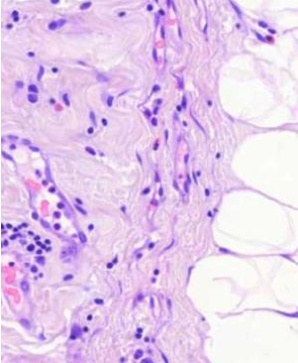

koagulaationekroosia

mitä nähdään tuumorin alueella? (vinkki: liposarkooma)

Liposarkooma

päättele kuvan avulla, mikä tauti on kyseessä?